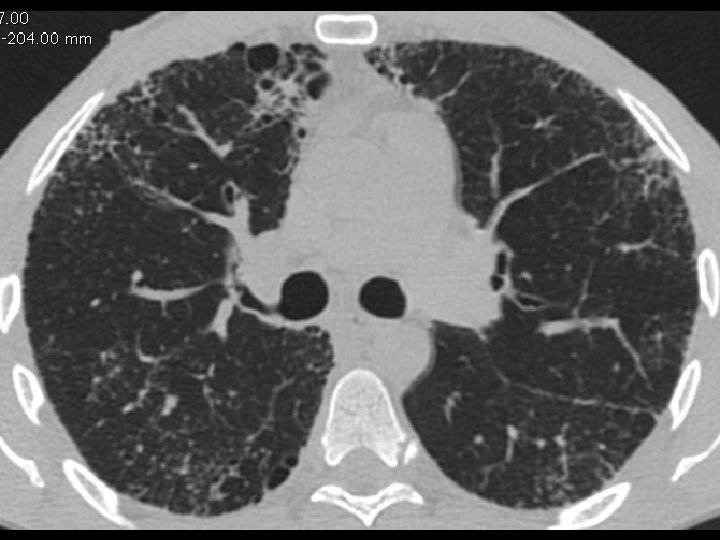

High-resolution CT scan

Subpleural, basal predominance Reticular abnormality Honeycombing with traction bronchiectasis UIPUIP Pattern

Subpleural, basal predominance Reticular abnormality Honeycombing with traction bronchiectasis Profuse micronodules UIPUIP Pattern Inconsistent with UIP Pattern

39 yo caucasian male, works in car collision repair and painting Multiple allergies, Gastroesophageal reflux disease and Thrombocytopenia of unknown etiology Smoker. No drugs CT: Reticular abnormality and honeycombing of subpleural basal predominance + micronodules Lung function tests: decreased diffusion capacity of the lung Blood tests: small increase of ESR and CRP; Autoimmune screening blood tests were normal BAL: normal celularity, with a mild increase in the neutrophil and eosinophil count

39 yo caucasian male, works in car collision repair and painting Multiple allergies, Gastroesophageal reflux disease and Thrombocytopenia of unknown etiology Smoker. No drugs CT: Reticular abnormality and honeycombing of subpleural basal predominance + micronodules Lung function tests: decreased diffusion capacity of the lung Blood tests: small increase of ESR and CRP; Autoimmune Screening Blood Tests were normal BAL: normal celularity, with a mild increase in the neutrophil and eosinophil count Definitive diagnosis can be established? Additional diagnostic tests required? Which tests?